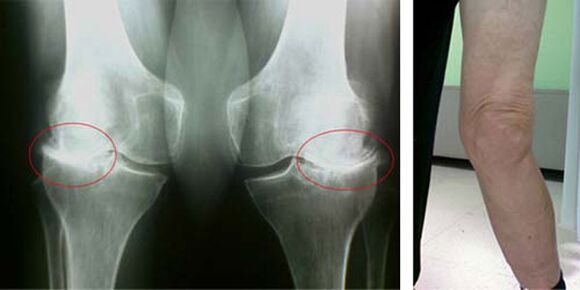

Le fasi iniziali del verificarsi di una tale patologia come l'artrosi dell'articolazione del ginocchio non si manifestano visivamente in alcun modo. Tuttavia, dopo un certo tempo, il paziente nota segni di deformità del ginocchio, nonché una caratteristica curvatura lungo l'asse della parte inferiore della gamba (diretta verso l'interno). C'è anche uno scricchiolio quando devi piegare la gamba.

La presenza di dolore, il movimento limitato del ginocchio fa sì che una persona veda un medico e si sottoponga a un esame. Per fare questo, deve superare i test e fare una radiografia dell'articolazione malata. Se queste misure non sono sufficienti per confermare l'artrosi dell'articolazione del ginocchio, viene eseguita la risonanza magnetica. Sulla base dei dati raccolti, il medico sceglie i migliori metodi di trattamento.